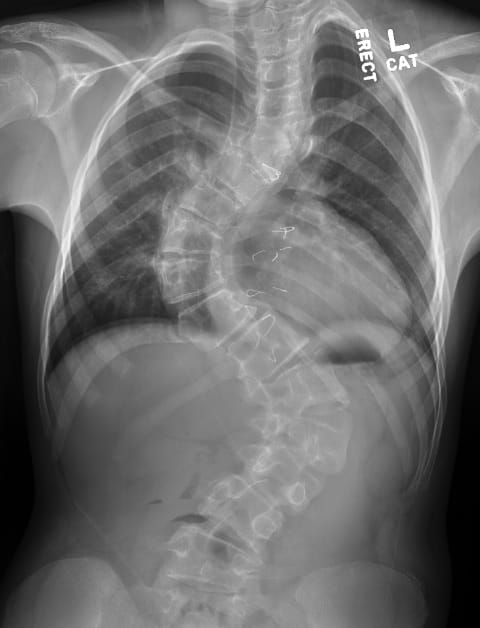

After wearing a brace or cast for most of her life due to congenital scoliosis, an 11-year old girl can now move freely, play sports and generally act like a typical preteen thanks to groundbreaking surgery.

The patient’s significant curve, caused by scoliosis and VATER Syndrome, a congenital defect that includes vertebrae abnormalities, made her a good candidate for Firefly.

Using Firefly, Dr. Hardesty was able to correct her patient’s spine from about a 90-degree curve to a 20-degree curve. “That would not have been achieved had I not been able to put two screws in at every level,” she says. “Without Firefly, I couldn’t have done that.”